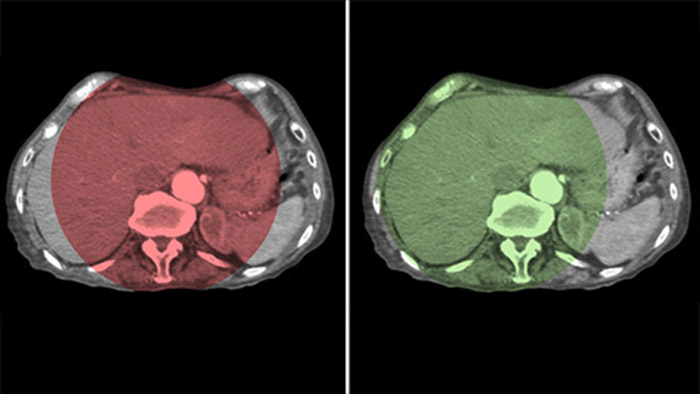

CBCT Dual permite la adquisición 3D de una fase arterial para visualizar estructuras vasculares y una post-arterial (fase retardada) para visualizar la acumulación de medio de contraste, en un solo paso automático5.

Dual View permite la visualización simultánea de dos conjuntos de datos CBCT. Tanto la fase arterial como la retardada pueden mostrarse una al lado de la otra o en una sola vista de superposición fusionada.